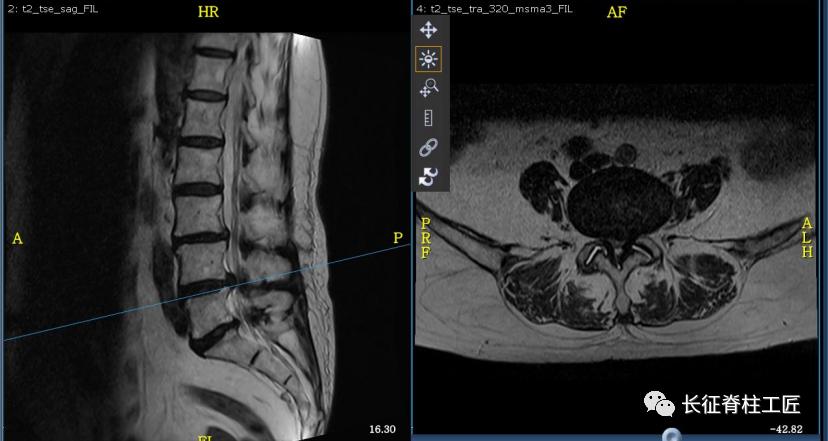

入院检查,腰部疼痛,后伸时加剧,局部压痛,双下肢肌力减退。X线检查,L4、L5骨质增生,MRI显示L4/L5、L5/S1椎间盘突出,马尾神经受压明显,被确诊为腰椎管狭窄症。

脊柱外科史国栋主任带领团队详细讨论,决定行椎管减压植骨融合内固定术。秉持微创的理念,术中通过精确的切口设计、肌肉组织的保护、手术时间的控制、后侧韧带复合体的保留等措施,在开放的手术中微创的完成了手术。